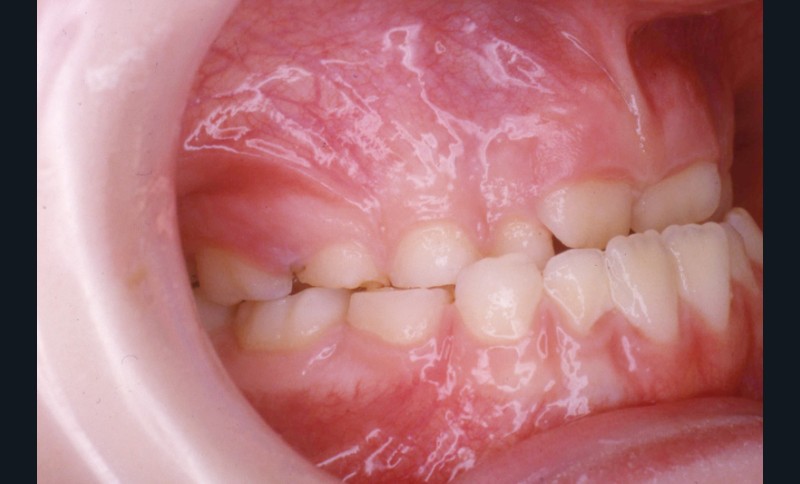

L’examen de la denture (fig. 3 à 5) montre :

• dans le sens antéro-postérieur, des relations molaires et canines de type classe III d’Angle et une inversion des rapports incisifs,

• dans le sens transversal, une endomaxillie bilatérale prédominante dans la région canine.